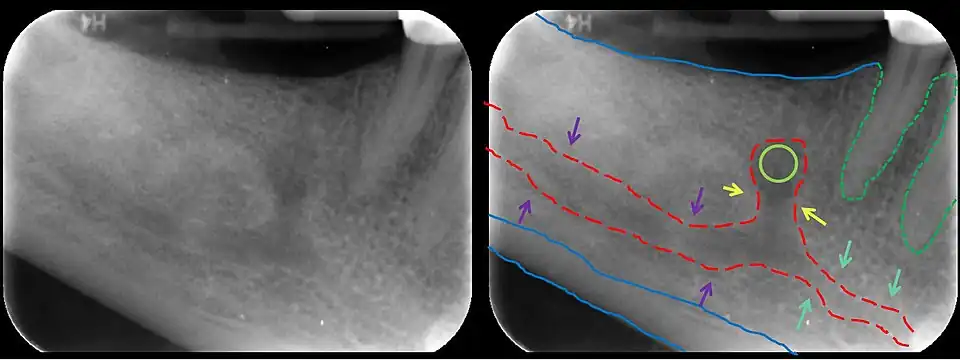

In human anatomy, the mandibular canal is a canal within the mandible that contains the inferior alveolar nerve, inferior alveolar artery, and inferior alveolar vein. It runs obliquely downward and forward in the ramus, and then horizontally forward in the body, where it is placed under the alveoli and communicates with them by small openings.

On arriving at the incisor teeth, it turns back to communicate with the mental foramen, giving off a small canal known as the mandibular incisive canal, which run to the cavities containing the incisor teeth.[1] It carries branches of the inferior alveolar nerve and artery.

The mandibular canal is continuous with two foramina: the mental foramen which opens in the mental region of the mandible and carried the distal fibres of the inferior alveolar nerve as the mental nerve; and the mandibular foramen on medial aspect of ramus, into which the mandibular nerve enters to become the inferior alveolar nerve. The mandibular canal often runs close to the apices of the third molar tooth, and the inferior alveolar nerve can become damaged during removal of this tooth, causing sensory disturbance in the distribution of the nerve. This is sometimes the case for the second or first molar teeth, and care must be taken during removal or root canal treatment in such cases to prevent nerve injury or extrusion of root canal filling materials.[2]

Variations

Several variations of the mandibular canal exist with varying frequency. The most common variant is the retromolar canal (~10 % of canals), whereby a branch is given off in the mandibular ramus which terminates in the retromolar region of the mandible. The retromolar canal may cause bleeding during surgery in the retromolar region such as removal of mandibular third molar teeth. Other variants include a bifid canal with a branch (~41%):[3] following the course of the main mandibular canal before re-joining it (forward or buccolingual type); terminating at the apex of a tooth, usually the molar teeth (dental type); opening as an accessory mental foramen.[4] A trifid mandibular canal variation has also been described.[5][6]